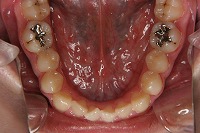

下顎

反対咬合と下顎が出ている事を主訴に来院された、初診時18歳1か月の男性です。診断「上顎骨の後方位による骨格性反対咬合」非抜歯での矯正治療と、下顎を後退させる外科手術を併用して治療を行いました。